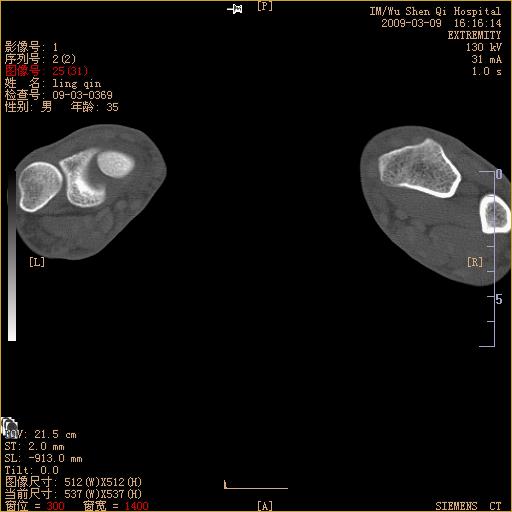

标题: CT18570:右手外伤10余天

请上传x线平片。舟状骨骨折可能大。

腕部有骨折、脱位,骨科面对ct片如何采取措施?三维一下。

请上传x线平片,腕骨多骨骨折

舟状骨骨折。

左侧舟骨及桡骨茎突骨折,第一掌骨基底部好像也有骨折,建议上传平片